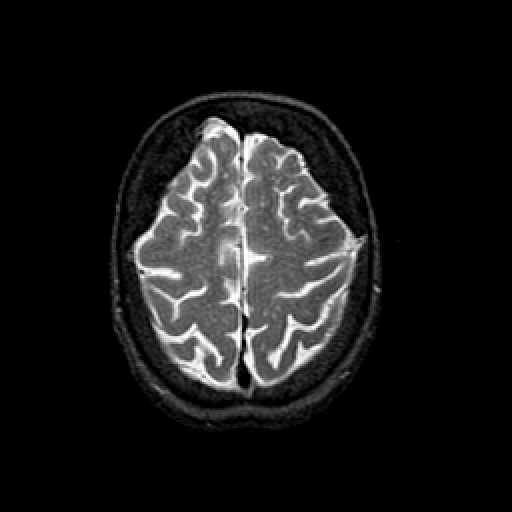

T2-weighted structural MR: Slice 42

Slice 42